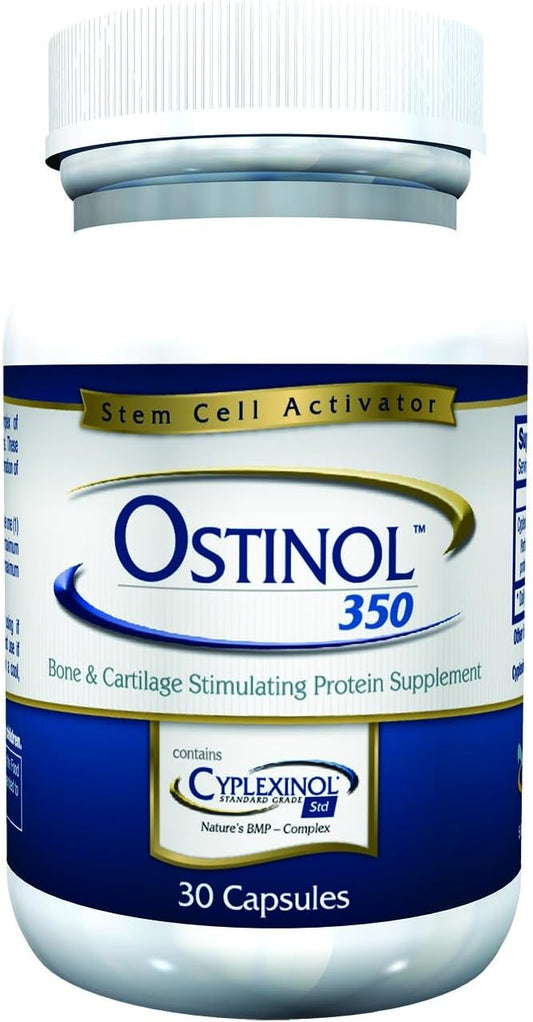

BULLET POINTS : 1 > DON'T JUST SUPPLEMENT, BIOACTIVATE with an all-natural stem cell signaling...

BULLET POINTS : 1 > DON'T JUST SUPPLEMENT, BIOACTIVATE with an all-natural stem cell signaling...

Manufacturer : Ostinol, Imported By : Esupli, Package Dimensions : 5.08 x 5.08 x 10.16...